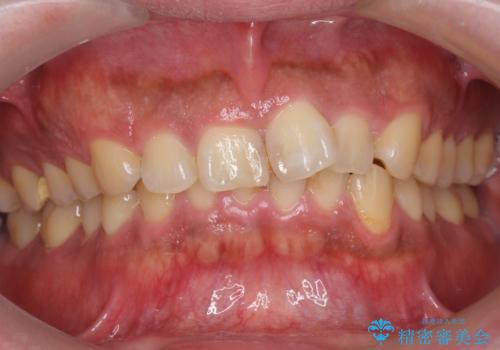

抜かない矯正 前歯がとび出ているのをマウスピースで

- 前歯のがたがたと出っ歯を主訴に来院。

CTを撮影したところ、臼歯部の頬側の骨の厚みが非常に大きく、通常では考えられない量の歯列の拡大が可能でした。

今回は健康を損なわずに非抜歯で治療が可能でしたが、

歯ぐきや骨の厚みが薄い他の患者さんでは難しいです。

左上5は180度捻転していましたので、そのまま並べています。

遠心移動などは行わず、IPRと拡大のみで治療を行いました。

一般的に非抜歯矯正を無理に行うと、口元がモッコリ出てしまうことがあります。しかし、今回は前歯を前に出さないような設定にしており、口元が出ることもありませんでした。